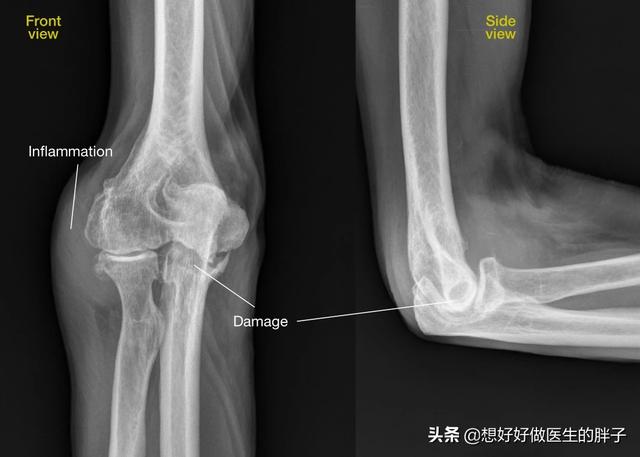

另外一种常见导致肘关节疼痛的原因是肘关节的骨关节炎。

其实临床上这样的患者也是比较多的,出现这种问题的人群多数都是平时对于肘关节使用比较多的重体力劳动者。在东北这边以农民和矿工多见。很多患者肘关节已经不能正常的进行屈伸活动了,但是即使这种情况也很少有人来看病,往往都是由于肘关节关节炎特别严重,而且出现了严重的畸形卡压到肘关节的神经,患者不能正常的拿筷子吃饭,或者是感觉到无力甚至等到出现肌肉萎缩我才到医院来治病。

此时被卡压的往往是在肘关节内侧走行的非常重要的一根神经,那就是尺神经。如果尺神经因为骨关节炎出现了卡压,会导致患者出现明显的手指肌肉的无力,尤其是不能夹纸,不能正常使用筷子,而且在手的部位会出现明显的凹陷,这就是肌肉萎缩的表现。

当患者出现了以上的症状,建议要到医院进行肘关节x线的检查,同时要进行肘关节肌电图检查,明确是否存在的是神经的卡压以及神经传导的异常,这种情况往往需要手术治疗解决,使神经受到的卡压,才能帮助患者真正的解决问题。